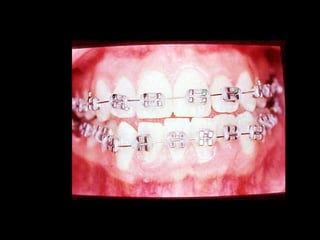

La paciente muestra una franca disgnatia, clínicamente

observamos malposición dentaria secundaria a la falta de

armonía máxilomandibular.

Marcada Clase III

Hábito Lingual

Sobremordida horizontal: –1.5 mm

Sobremordida vertical: + 1 mm.